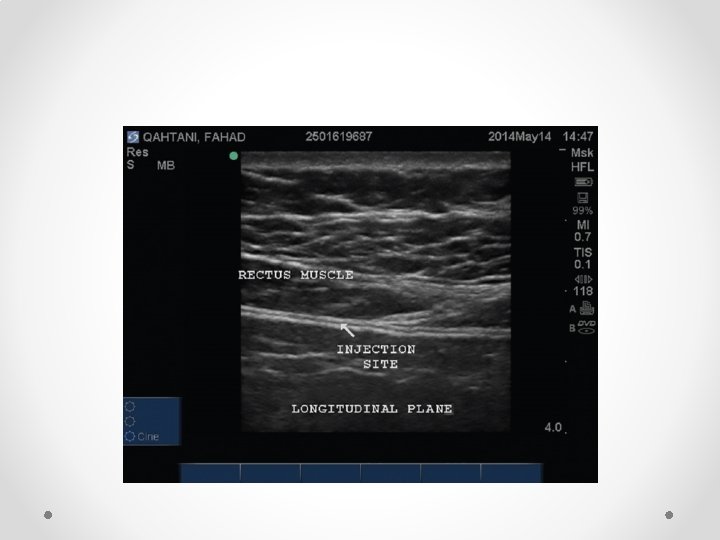

Rectus Sheath block for ACNES

Nerves run between IOM and Transversus abdominus, then posterior to rectus muscle before perforating through it to skin

Above (top) and below arcuate line NB below arcuate line (5 -10 cm below umbilicus) is no fascial sheath deep to rectus abdominus